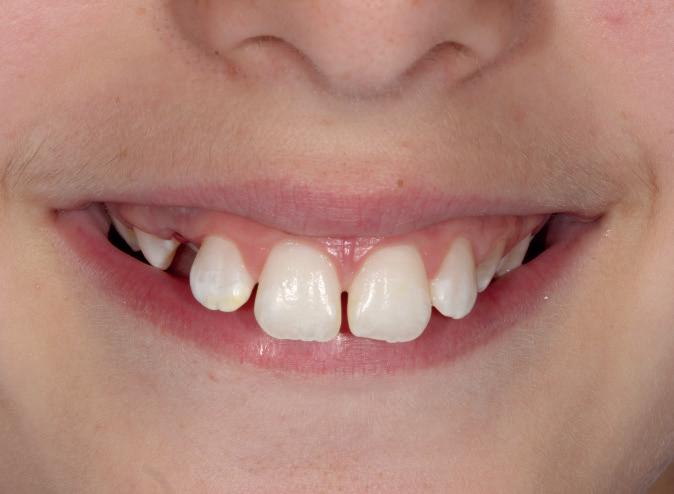

Rise of the Internet dental diagnosis

From the bizarre, and the ridiculous to the positively dangerous, online ‘dentistry’ has been blooming in popularity

Reams of misinformation and wrong claims abound on the internet. You can visit sites such as TikTok to investigate all the ways people are putting their smiles in danger.

Influencers are recommending rubbing fruit like strawberries and lemons on their teeth constantly to whiten them. Filing their teeth with a nail file so they look straighter. Using nail glue to fix their loose teeth to the gums.

These examples are certain to send a shudder of horror through any dental professional when their patients admit to attempting them. These types of DIY dentistry can cause permanent damage to patients’ mouths.

More importantly, these practices can cause pain and be costly to correct, putting pressure on the dentist to perform miracles and undo the damage.